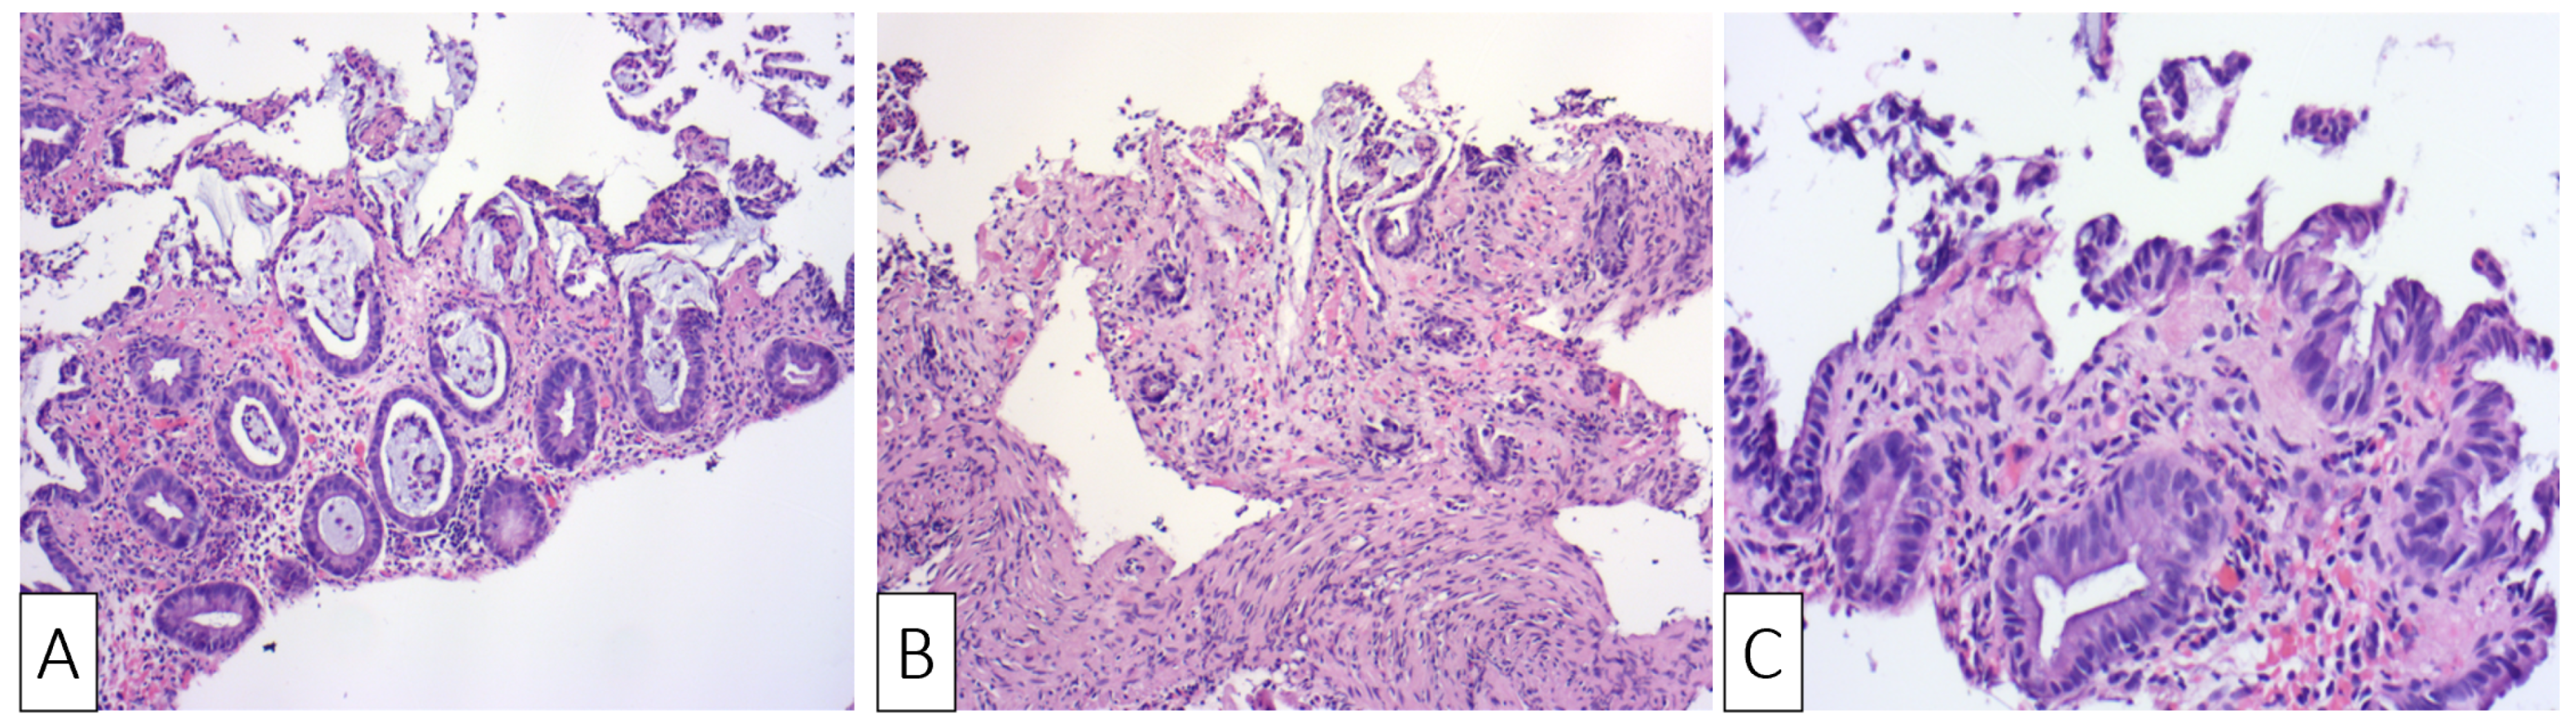

| Our patient | Male, 30 | Colicky left lower quadrant abdominal pain and bloody diarrhea | Negative fecal culture, positive toxins A, B, and GDH | Idiopathic | Several superficial longitudinal ulcerations with luminal narrowing spanning from sigmoid to the descending colon | Desquamation of superficial epithelium with focal necrosis, loss of superficial glands, edematous and necrotic lamina propria | Oral Vancomycin, symptoms resolved within two days of hospitalization |